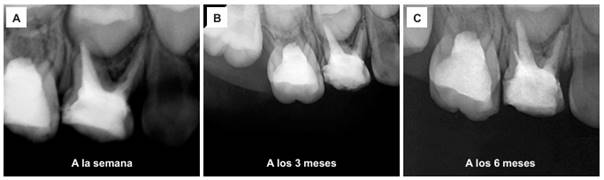

Una semana después, en la cita de control, la paciente no presentó dolor a la percusión vertical durante el examen clínico. Asimismo, se identificó movilidad dentaria de grado 1, determinada mediante presión en sentido vestíbulo-palatino con dos instrumentos metálicos. Radiográficamente, se observó una IRO intraconducto compatible con la obturación de los conductos radiculares, así como una IRL a nivel interradicular con pérdida de la lámina dura y ensanchamiento del espacio del ligamento periodontal en la superficie distal de la raíz mesiovestibular (figura 4A).

Tres meses después, la paciente mostró las mismas características clínicas y radiográficas (figura 4B). A los seis meses, no presentó molestias, dolor ni movilidad dental, y no se evidenciaron manifestaciones clínicas de procesos infecciosos de origen dentario. Radiográficamente, se observó una disminución del ensanchamiento del espacio del ligamento periodontal en la superficie distal de la raíz mesiovestibular, así como la ausencia de IRL a nivel interradicular, lo que indica la reparación de la lámina dura (figura 4C).

Figura 4 Controles radiográficos después del retiro del instrumento. A y B) A la semana y a los 3 meses: imagen radiolúcida a nivel interradicular con pérdida de lámina dura. Ensanchamiento del espacio para el ligamento periodontal en superficie distal de raíz mesiovestibular. C) A los 6 meses: disminución del ensanchamiento del espacio para el ligamento periodontal en superficie distal de raíz mesiovestibular, ausencia de imagen radiolúcida a nivel interradicular.